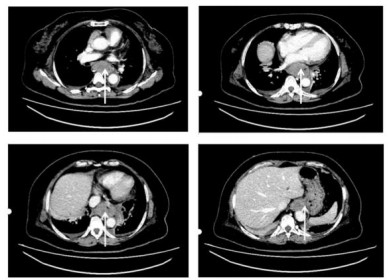

入抢救室生命体征:体温36.5 ℃,血压116/75mmHg(1 mmHg=0.133 kPa),心率104次/min,SpO2 96%(不吸氧)。神清,气稍急,双肺呼吸音粗,未及明显干湿啰音。腹软,左上腹有压之不适感,Murphy征阴性,麦氏点无压痛及反跳痛,双下肢不肿。完善相关检查,血红蛋白90 g/L,红细胞压积26.0%,平均红细胞体积97.0 fL,平均血红蛋白量33.6 pg,平均血红蛋白浓度346 g/L,血小板185×109/L, 白细胞计数18.39×109/L,中性粒细胞百分比77.9%。血氨、乳酸正常。D-二聚体1.59 mg/L,C反应蛋白90 mg/L;降钙素原、肝肾功能电解质、心脏标志物:均正常。心电图正常。门静脉CT检查未见异常;食管下段肿胀、管壁增厚,需结合内镜检查;肝及左肾囊肿,胆囊结石,升结肠憩室;两侧胸腔积液。胃镜示全食管巨大血肿,延续至贲门口(会厌部至贲门口见巨大血肿,表面可见纵行裂口,内见血块及坏死物,未见明显活动性出血;贲门口见血块,无明显曲张静脉)(图 2)。

| 图 2 患者治疗前胃镜示全食管巨大血肿,延续至贲门口 |

请多学科(外科、内科、介入科、内镜中心)会诊后,均建议内科保守治疗。给予病危通知,禁食、止血、补液、营养支持及对症治疗后,患者胸骨后持续性疼痛逐渐缓解,呕血明显减少至停止,随访血红蛋白逐渐上升。2周后来院随访血红蛋白118 g/L,随访胃镜:食管距门齿26 cm至贲门见瘢痕改变,余所见食管黏膜正常,齿状线清晰,高位倒转胃底贲门无异常;胃体黏膜稍充血,胃角光滑无溃疡;胃窦体交界处见一大小约1.2 cm息肉,胃窦部蠕动正常;幽门口圆,开闭好。十二指肠球部无溃疡无畸形,降部伸入未见异常(图 3)。

| 图 3 患者治疗2周后胃镜示食管疤痕改变,食管黏膜粗糙 |